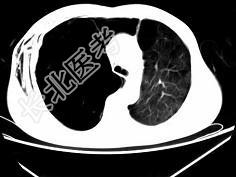

- 单项选择题男,32岁, 被车撞伤后1小时,请结合影像图像选择其最可能的诊断为 ( )

A、右侧气胸

B、右肺不张

C、右侧气胸并皮下纵隔气肿

D、右侧肺大疱并皮下纵隔气肿

E、支气管断裂